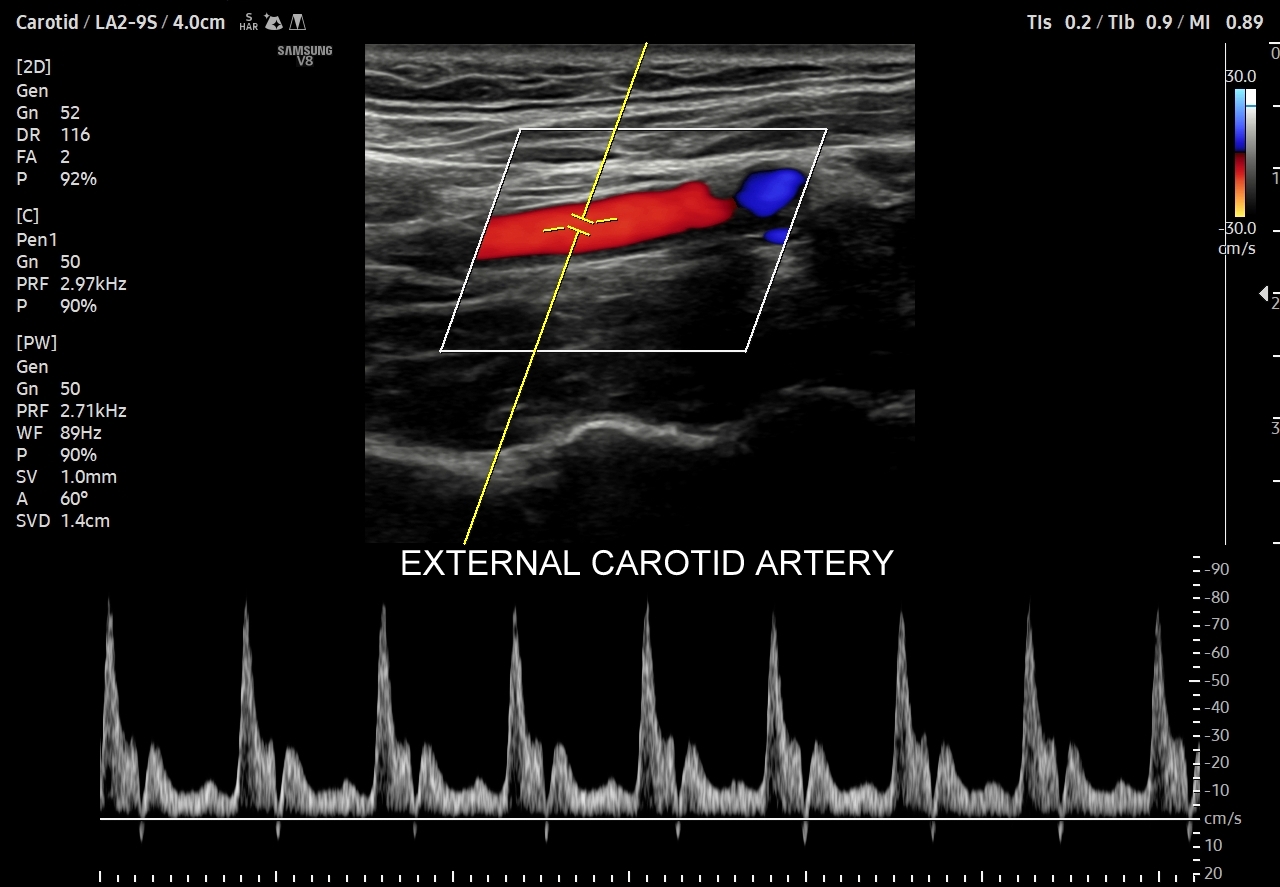

- Profile o umiarkowanej pulsacyjności różnią się od wcześniej omówionych tym, iż przepływ w fazie rozkurczowej utrzymuje się, jednakże ma niższe prędkości i może być przerwany drobnym, wczesnodiastolicznym odwróceniem przepływu. Profile tego typu występują w tętnicach unaczyniających np. twarz, jelita, trzustkę.

Profil przepływu tętniczego cechuje się pulsacyjnością. W składu pulsu wchodzi składowa skurczowa i rozkurczowa. Składowa skurczowa rejestrowana jest we wszystkich drożnych tętnicach i jest zależna głównie od prawidłowo funkcjonującego serca. Składowe rozkurczowe, a konkretnie kształty spektrum prędkości przepływu krwi w naczyniach w trakcie rozkurczu komór serca, różnią się w zależności od łożyska naczyniowego. Otóż składowa rozkurczowa zależy przede wszystkim od unaczynionej przez tętnicę tkanki bądź narządu, a także od kurczących się elastycznych tętnic. Pomiędzy składową skurczową a rozkurczową często obserwuje się złamki odpowiadające chwilowemu wstecznemu przepływowi krwi związanemu z zamykaniem się zastawek aortalnej bądź płucnej, jak i odbiciem się fali tętniczej od naczyń na poziomie mikrokrążenia (ang. water-hammer effect). Biorąc pod uwagę kształt fali spektrum przepływu możemy je podzielić na te o 1/ niskiej pulsacyjności, 2/ umiarkowanej pulsacyjności, 3/ wysokiej pulsacyjności.

Oprócz przepływów typowo niskooporowych oraz typowo wysokooporowych istnieją profile przepływów o pośredniej charakterystyce, np. w tętnicy szyjnej wspólnej. Z kolei w przypadku tętnic kręgowych w zależności od ich szerokości fizjologicznym jest obserwowanie zarówno profilu niskooporowego w przypadku dużej średnicy, jak i wysokooporowego w przypadku małej średnicy.